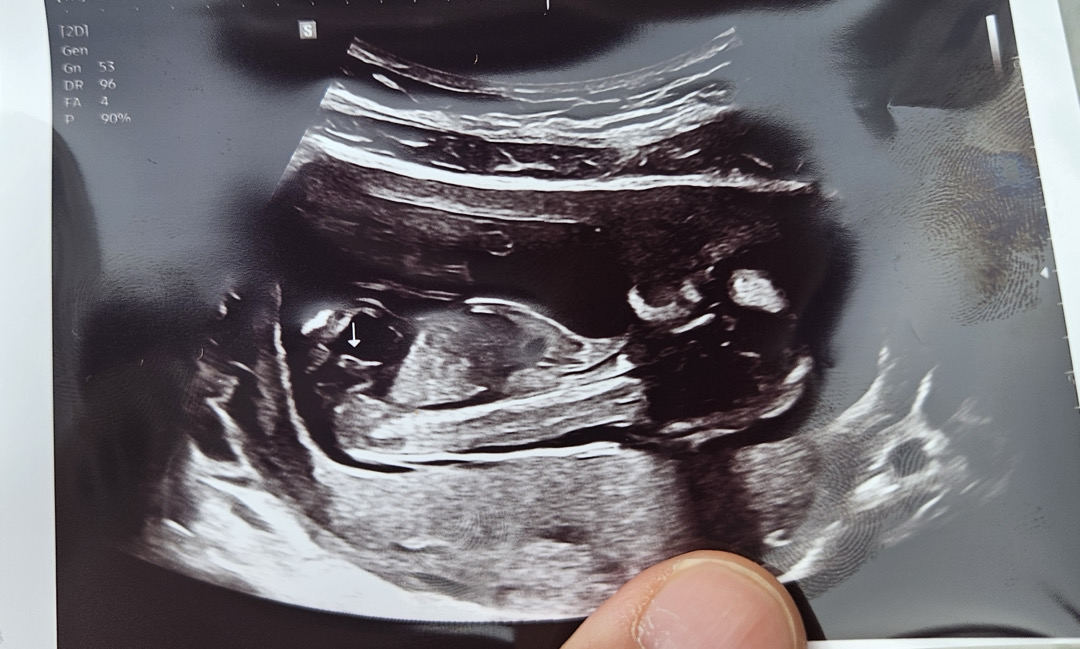

12주차 5일 각도법 좀 봐주세요! :-)❤️

왼쪽 측면 사진입니다.^^ 각도법으로 잘 맞추시는 전문가님들 부탁드립니다! :)

안녕하세요. 글쓴이입니다^^ 16주가 되어 오늘 성별을 알게됬습니다. 아들맘 당첨됬어요! :) 답변해주신 전문가님들 감사합니다.